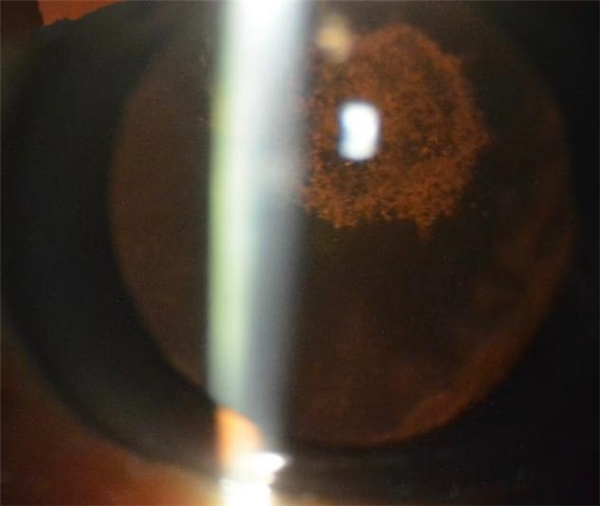

药物与中毒性白内障的混浊位置、形态极具特异性,裂隙灯检查可快速区分:

糖皮质激素性白内障

典型表现:后囊膜下“锅巴样”盘状混浊,初期为细点状、浅棕色条纹,伴彩色反光与空泡,逐渐融合成盘状,逆光、强光下视力骤降、眩光明显;少数早期停药可部分逆转,成熟后无法恢复。

氯丙嗪性白内障

混浊位于前囊膜下,呈白色/黄褐色星状、花瓣状微粒沉着,瞳孔区色素明显,伴随角膜内皮色素沉积。

TNT中毒性白内障

职业暴露2年以上高发,初期晶状体成人核与前后皮质点状混浊,逐渐发展为环形、楔形、盘状,最终全晶状体混浊,伴金属光泽反光。

缩瞳剂性白内障

早期前囊膜下微细囊泡,晚期后囊膜下混浊,常与青光眼本身病变叠加,易漏诊。

重金属中毒性白内障

多为皮质深层颗粒状混浊,伴彩色结晶反光,可合并视网膜、视神经毒性损伤。